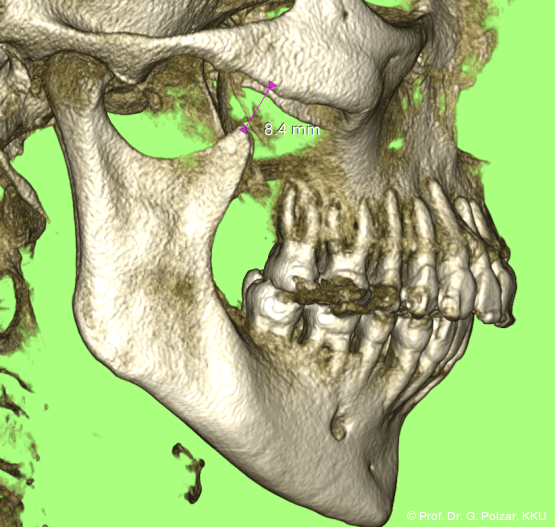

KG-Position: Die 3D-Ansicht im DVT zeigt eine vorverlagerte UK-Position bei neutraler Okklusion (Abb. 4a+b).

Im Sagittalschnitt zeigen beide Kiefergelenke eine deutlich anteriore Position. Der dorsokraniale Abstand betrug rechts 7,0 mm und links 5,8 mm. In der PEP waren sie im lateralen Bereich ca. 1 mm kleiner als in der Mitte der Sagittalprojektion (Abb. 6a–d).

Diese deutlich anteriore Gelenkposition im Neutralbiss ließ den Verdacht auf einen Sunday Bite zu. Das heißt, die Patientin schob den Unterkiefer aktiv nach vorne, um damit schönere Schneidezahnkontakte bzw. eine vermeintlich neutrale Okklusion zu erreichen. Nach mühsamen Lockerungsübungen gelang es der Patientin, auch in die zen­trale Kiefergelenkposition zu wechseln. So zeigte sich das ganze Ausmaß der Malokklusion. In neutraler KG-Position hatte die Patientin eine sagittale Frontzahnstufe von ca. 7 mm mit 1 PB Klasse II-Okklusion im Seitenzahn­bereich (Abb.5a+b, 7a–c).

Nach der Umstellungsosteotomie mit der UK-­Vorverlagerung kann die Patientin besser zubeißen. Bei maximaler Interkuspidation in neutraler Okklusion befinden sich nun beide Kiefergelenke in zentraler Po­sition zur Gelenkpfanne. Der geringe Abstand des Caput mandibulae zur Schädelgrube lässt auf eine Diskusverlagerung schließen (Abb. 20a+b).